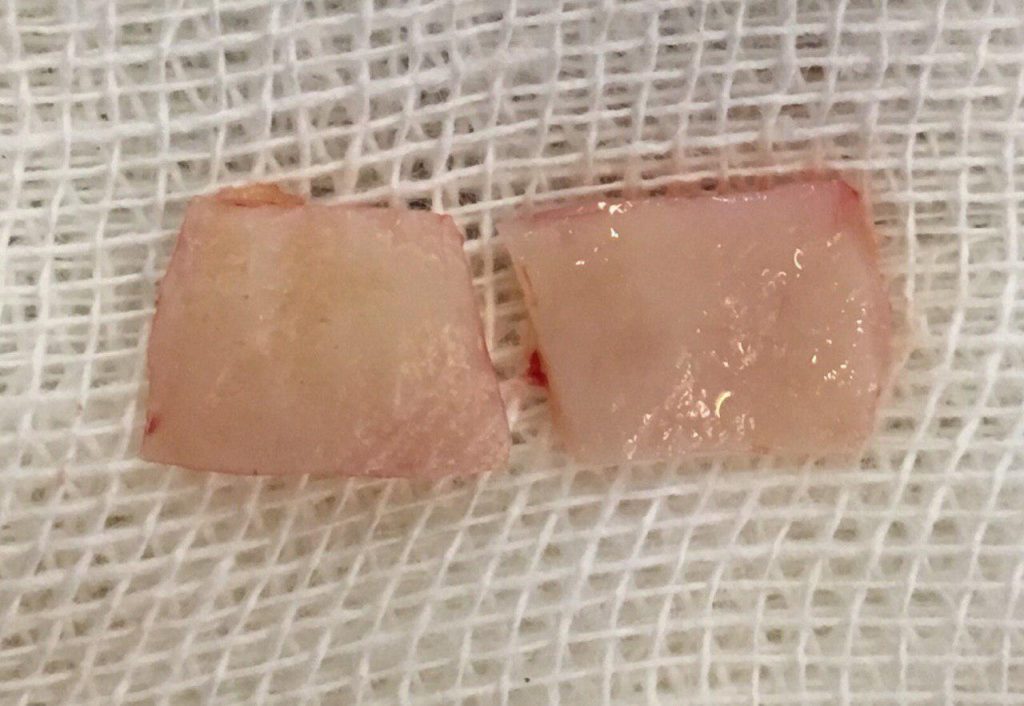

جراحی پیوند لثه جهت افزایش لثه چسبنده و پوشش ریشه و بهبود تحلیل لثه